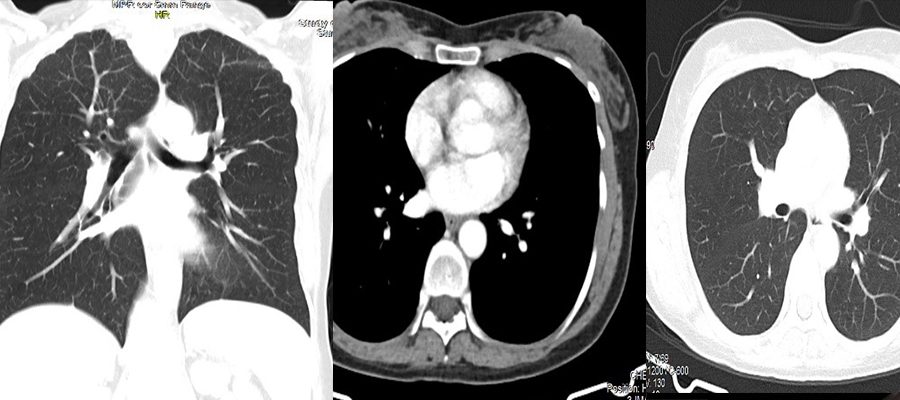

THORAX (Göğüs-Akciğer) Tomografi

Günümüzde akciğer ve hava yollarının hastalıklarını en iyi gösteren tetkik tomografidir.

Thorax BT ‘de mediasten denilen göğüs boşluğunda yer alan kalp,soluk borusu, yemek borusu, kalpten çıkan ana damarsal yapılarla birlikte akciğer ve akciğeri oluşturan hava kesecikleri hakkında bilgi sahibi oluruz.

Akciğerlerin hava ile dolu olması sebebiyle tomografi dışındaki tetkikler akciğerin bu kendine has yapısını bu kadar detaylı gösteremezler.